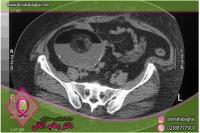

کیستهای تخمدان ساکهایی حاوی مایع هستند که درون تخمدان یا روی آن رشد میکنند. انواع مختلفی از کیستهای تخمدان وجود دارد که شایعترین آن کیستهای فولیکولی است که در یکی از فولیکولهای تولیدکننده تخمک ایجاد میشود. کیستهای ساده (فولیکولی) با رشد قسمتی از تخمدان و تجمع مایع داخل آن مشخص میشوند، اندازه آنها معمولاً بالای ۳ سانتیمتر است و نباید با فولیکول تخمک که در زمان تخمکگذاری گاهی حتی به اندازه ۲۵ میلیمتر میرسد، اشتباه شوند. بیشتر این کیستها خودبه خود یا با مصرف قرصهای پیشگیری از بارداری در خلال ۶ تا ۸ هفته از بین میروند و اغلب موجب بروز مشکلی نمیشوند البته گاه موجب درد شکمی میشوند.

کیستهای مرکب با حضور تیغه یا سپتوم در داخل کیست در سونوگرافی مشخص میشوند که آنها را به حفرههای متعدد تقسیم میکند؛ به طوری که کیست چند حفرهای ایجاد میشود.

تشخیص بیماریها و اختلالات مربوط به تخمدانها، از طریق آزمایشاتی مانند سونوگرافی انجام میشود. این آزمایشات در کلینیک دکتر وهاب آقایی با استفاده از آخرین تجهیزات تصویربرداری تشخیصی انجام میشود.